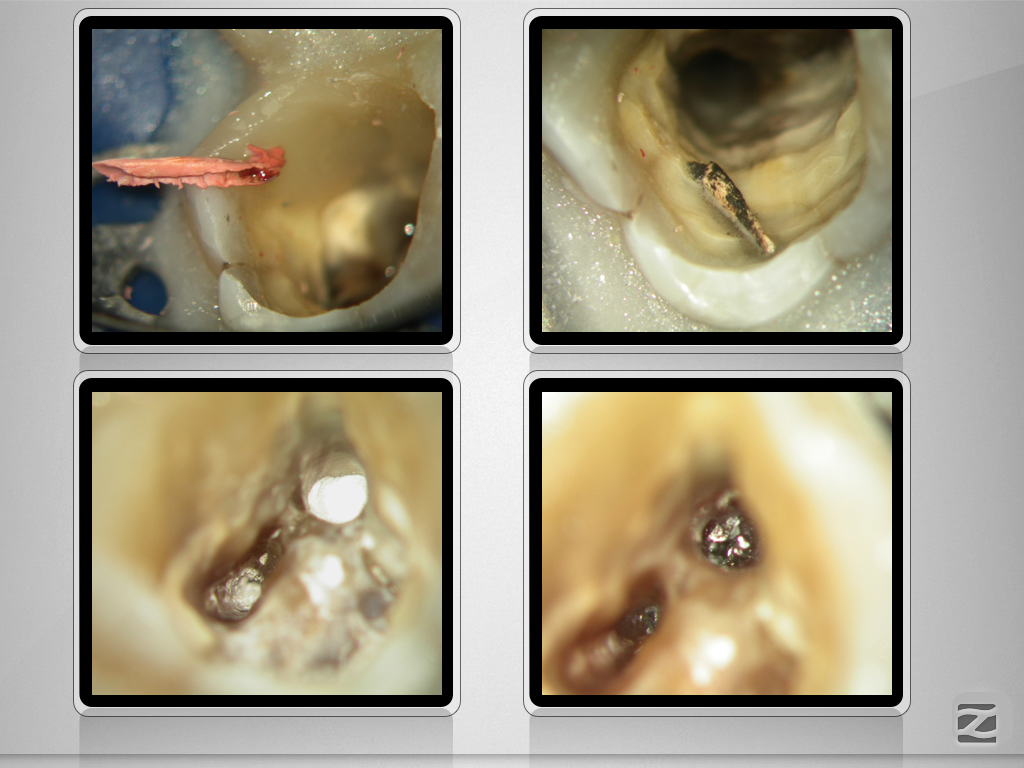

16D.007

Multiple Fragmente